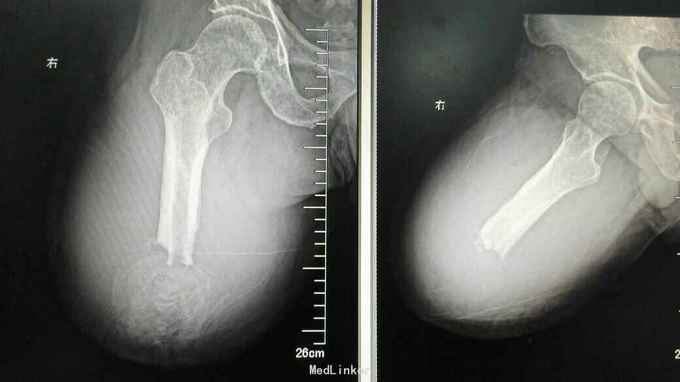

随访半年后肿瘤局部复发,再次行PET-CT检查排除远处转移后行右侧半骨盆离断术,目前术后3月,恢复良好,暂未见复发和转移 讨论:滑膜肉瘤为恶性程度很高的软组织肿瘤,局部复发率高,远处最易出现肺转移,文献报道5年生存率仅20%~40%。由于滑膜肉瘤对放化疗不太敏感,手术切除为目前最有效治疗手段,所以手术应尽可能切除干净,手术范围应该包括切除肿瘤所在间室肌肉全部,从而减少术后复发。